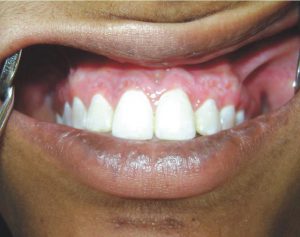

- Depigmentation

- Dr. Trusha Pednekar, a 3rd year PG student, won the Best Poster Presentation Award at the Goa State IDA Conference 2024 for the poster titled “Gingival depigmentation and esthetic approach of unmasking the hyperpigmented gingiva: A case series”.